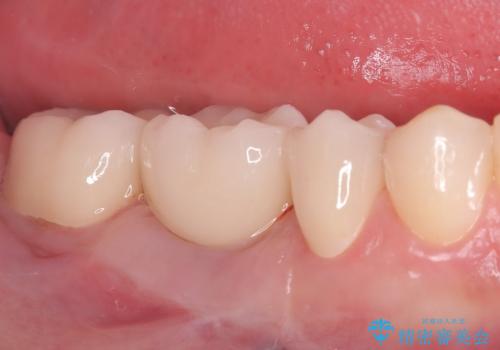

奥歯の銀歯を美しく一新!歯の破折を防ぐセラミッククラウン

担当医 河口智英